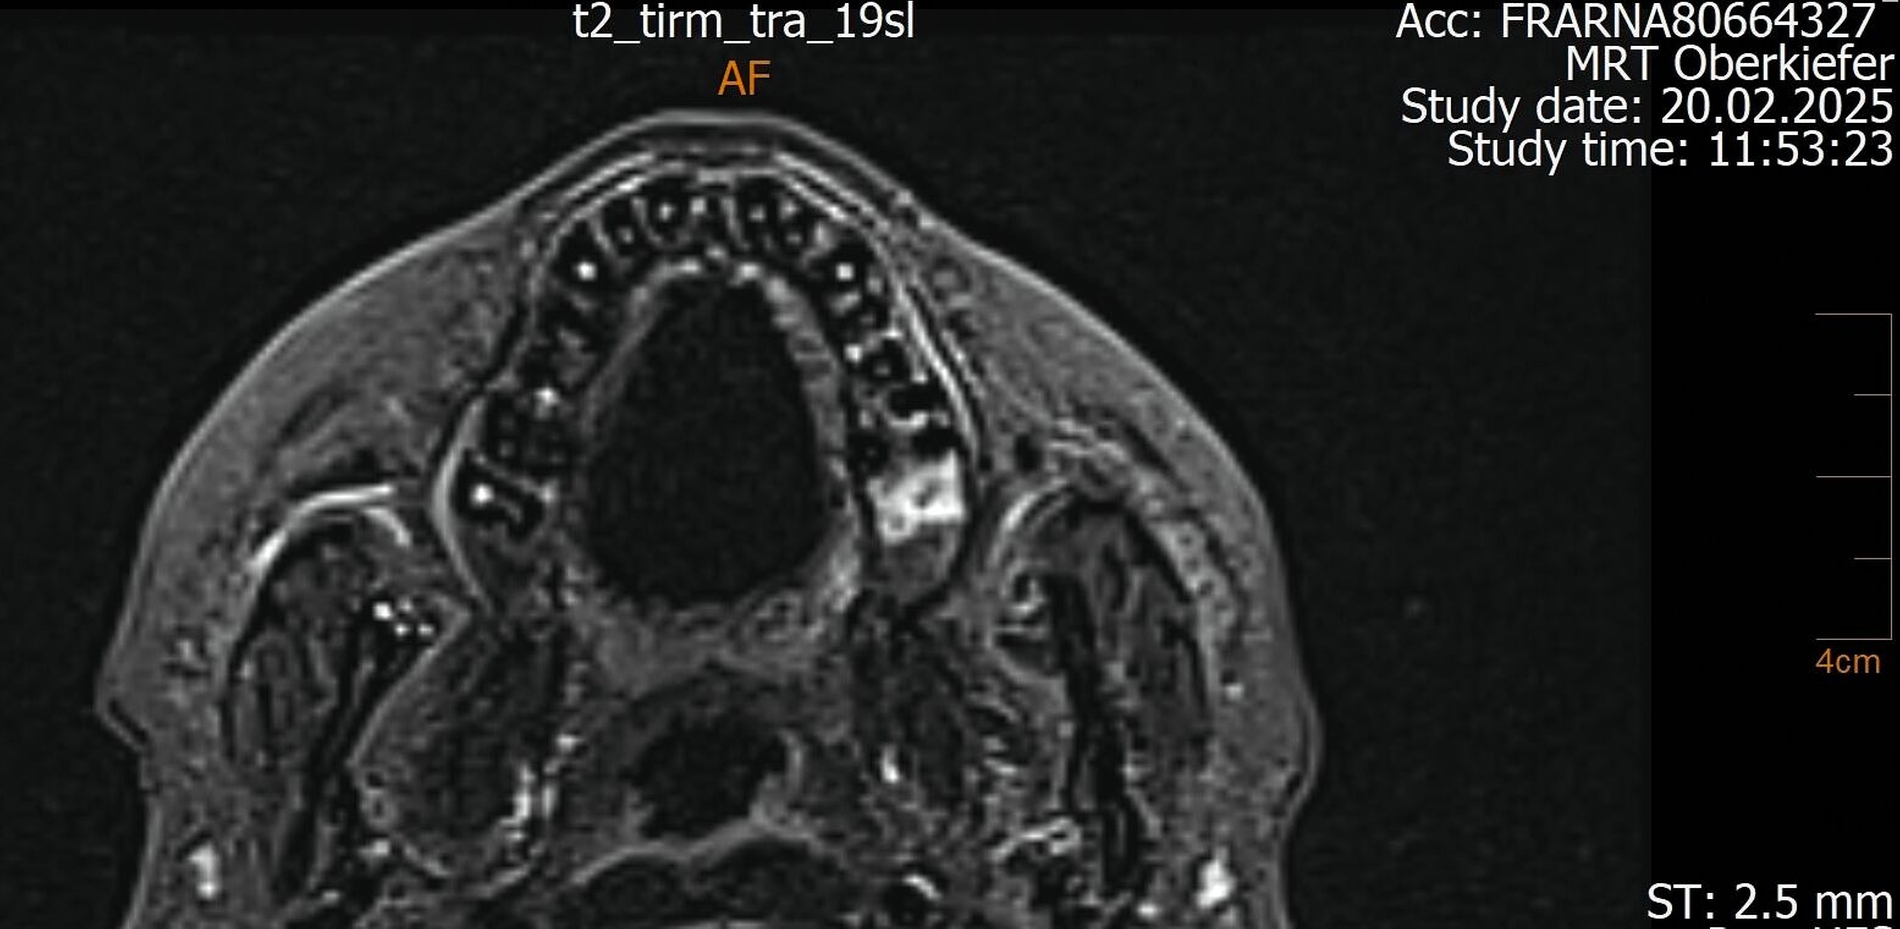

Der Wendepunkt erfolgte schließlich im Februar 2025 im Rahmen einer Kontrolluntersuchung bei der Hauszahnärztin. Diese nahm die langjährige Beschwerdesymptomatik ernst und veranlasste eine MRT-Untersuchung am Deutschen Zentrum für Dentaldiagnostik (DZD). Die MRT-Bildgebung ergab eine chronische Osteomyelitis im Bereich der Extraktionsregion von Zahn 27 sowie eine ausgeprägte apikale Ostitis an Zahn 26 mit vollständiger Verschattung der linken Kieferhöhle und Ausdehnung der Entzündung ins Siebbein und in die Stirnhöhle. Auch konnte durch den befundenden Radiologen eine interradikuläre Fistelung an Zahn 26 erkannt werden, weshalb die Sinusitis als odontogen eingestuft wurde (Abbildungen 4 bis 7).